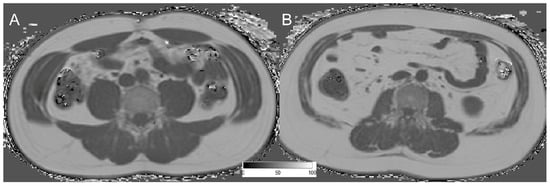

2.2. MR Imaging (T2 mDixon Quant)

2.3. PDFF Mapping